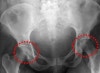

X-ray

병의 초기에는 정상 소견을 보입니다.

증상 발현 3~6주 후에는 골밀도 감소 소견을 보여 X-ray상 아래와 같은 현상이 나타납니다.

① Focal reduced bone density(국소적 골밀도의 감소)

② Subchondral lucent line(연골하 밝은 선)

③ Flattening(관절 편평화)

④ Step off(관절의 급격한 경사)